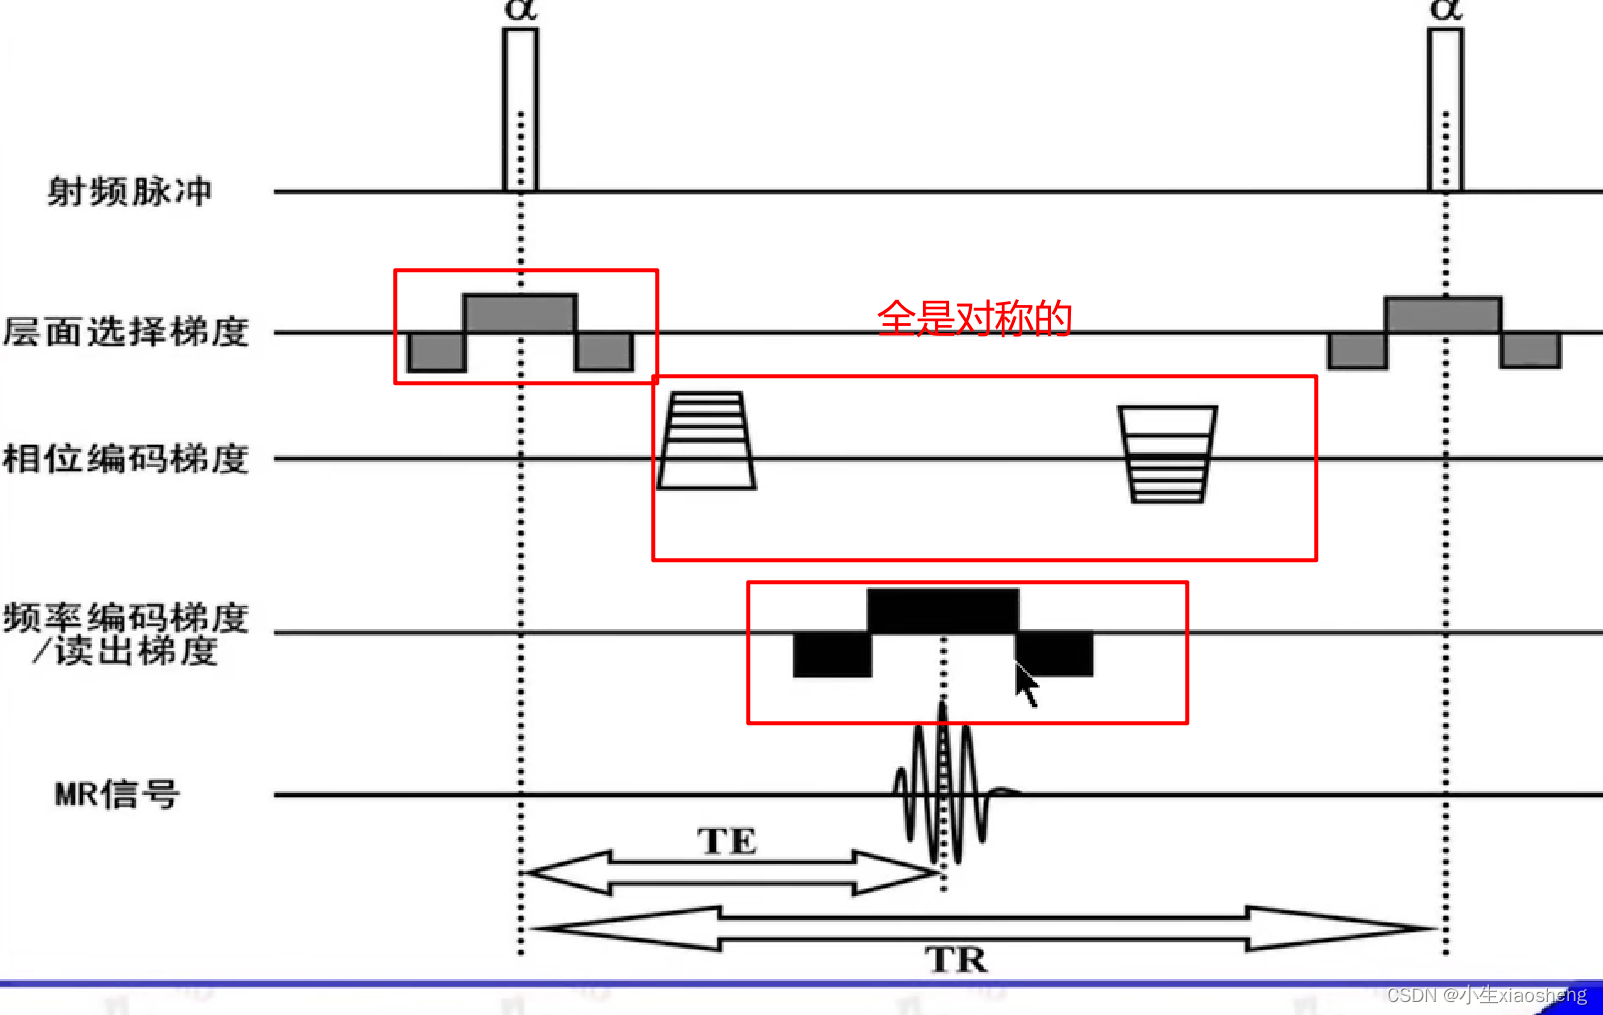

2.普通SSFP序列

梯度场抵消:SSFP序列的一个显著特点是,在Gx、Gy、Gz三个方向梯度场的正反切换完全抵消。这种抵消作用使得流动的信号得到补偿,从而在图像中减少或消除流动伪影。

TR和TE要小一点能得到更好的效果图片。